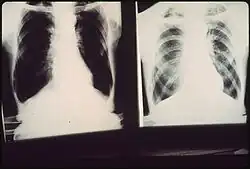

![]() zdjęcie radiologiczne płuc z obrazem pylicy płuc górników węgla (zdjęcia pacjentów dr. A.H.Russakoffa specjalisty pulmonologa i pioniera walki z zanieczyszczeniem powietrza) | |